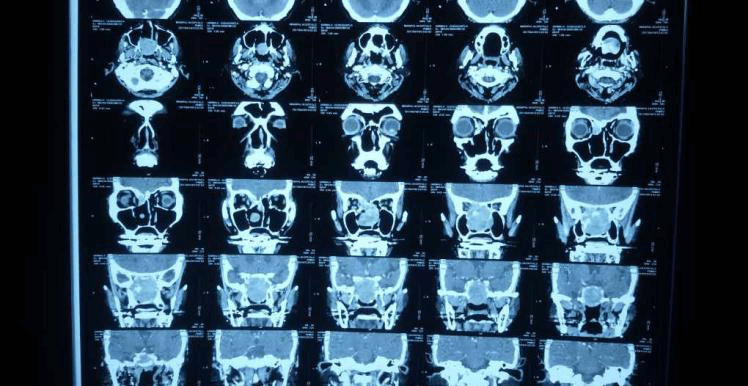

তিনি প্রথমে যশোদা হাসপাতালে ওপি হিসাবে এবং পরে স্থানীয় ইএনটি-এর সাথে অনুসরণ করেছিলেন। দুই বছর পর তার আমাদের সফরের সময় পুনরাবৃত্তির কোনো প্রমাণ পাওয়া যায়নি। এখন তিনি এপ্রিল মাসে আমাদের কাছে উপস্থাপন করেছিলেন যে এক সপ্তাহের জন্য ডান দিকের নাক দিয়ে রক্তপাত হচ্ছে। DNE ডানদিকে একটি অনিয়মিত মসৃণ পৃষ্ঠ ভাস্কুলার ভর দেখিয়েছে। CT PNS অনুনাসিক গহ্বরের পিছনের অংশে নরম টিস্যু ভর দেখায় যা ছাদ পর্যন্ত প্রসারিত হয় (ক্রিব্রিফর্ম প্লেট) এবং উপরে স্ফেনয়েড সাইনাস এবং নীচে নাসোফ্যারিনক্স পূরণ করে। তাকে রেডিওথেরাপি বিভাগে রেফার করা হয়েছিল যেখানে তাকে মস্তিষ্ক এবং কক্ষপথের নৈকট্যের কারণে IMRT-এর পরামর্শ দেওয়া হয়েছিল।